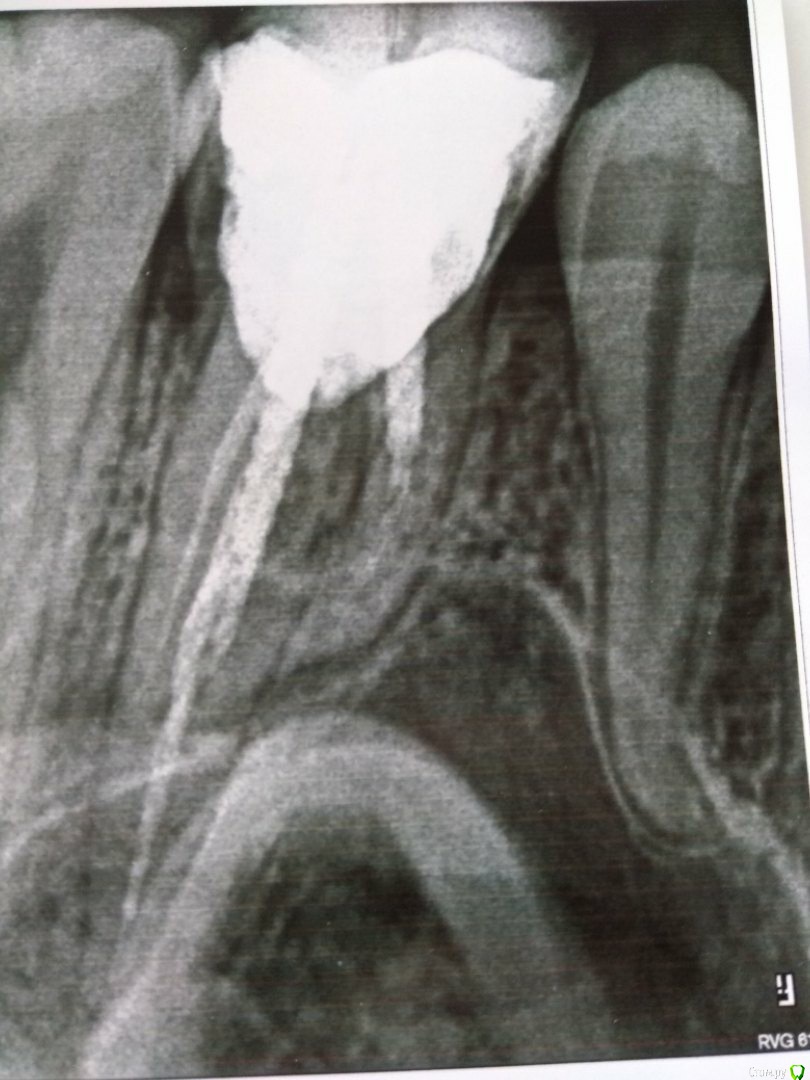

Katerina09 Опубликовано 4 марта, 2018 Поделиться Опубликовано 4 марта, 2018 Здравствуйте, в 26 зубе стоит штифт. Сам зуб не беспокоит, но потемнел у основания немного. Стоит ли переделывать всё и ставить коронку? Мне говорили, что один из каналов плохо запломбирован. Настолько это опасно?Что бы Вы посоветовали? Ссылка на комментарий

red_butler Опубликовано 4 марта, 2018 Поделиться Опубликовано 4 марта, 2018 Что бы Вы посоветовали? убрать пломбу и оценить объем оставшихся твердых тканей и перспективу протезирования. Если протезирование возможно, то повторное лечение корневых каналов и вкладка/коронка. Ссылка на комментарий